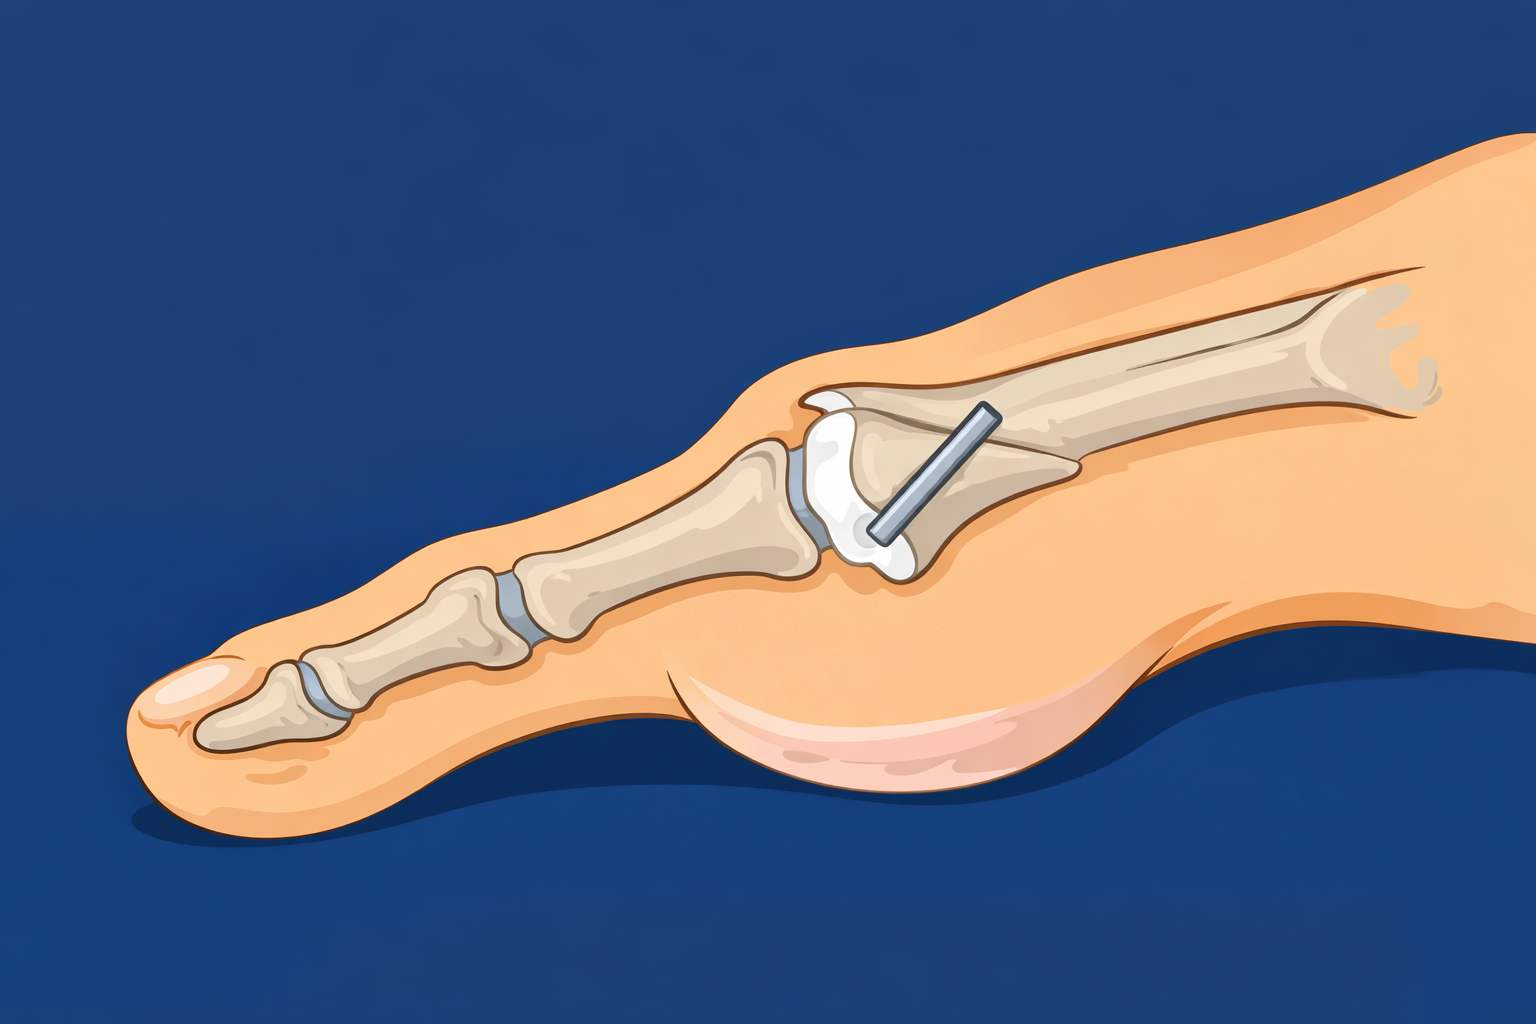

Bunion Correction and Forefoot Procedures Bunion Correction Bunion Correction 1st MTP joint decompression osteotomy 1st MTP joint decompression osteotomy Cheilectomy Cheilectomy Plantar Plate Repair Plantar Plate Repair 5th Metatarsal Osteotomy (Bunionette Correction) 5th Metatarsal Osteotomy (Bunionette Correction) Metatarsal Osteotomy Metatarsal Osteotomy Hammertoe Correction Hammertoe Correction Sesamoidectomy Sesamoidectomy